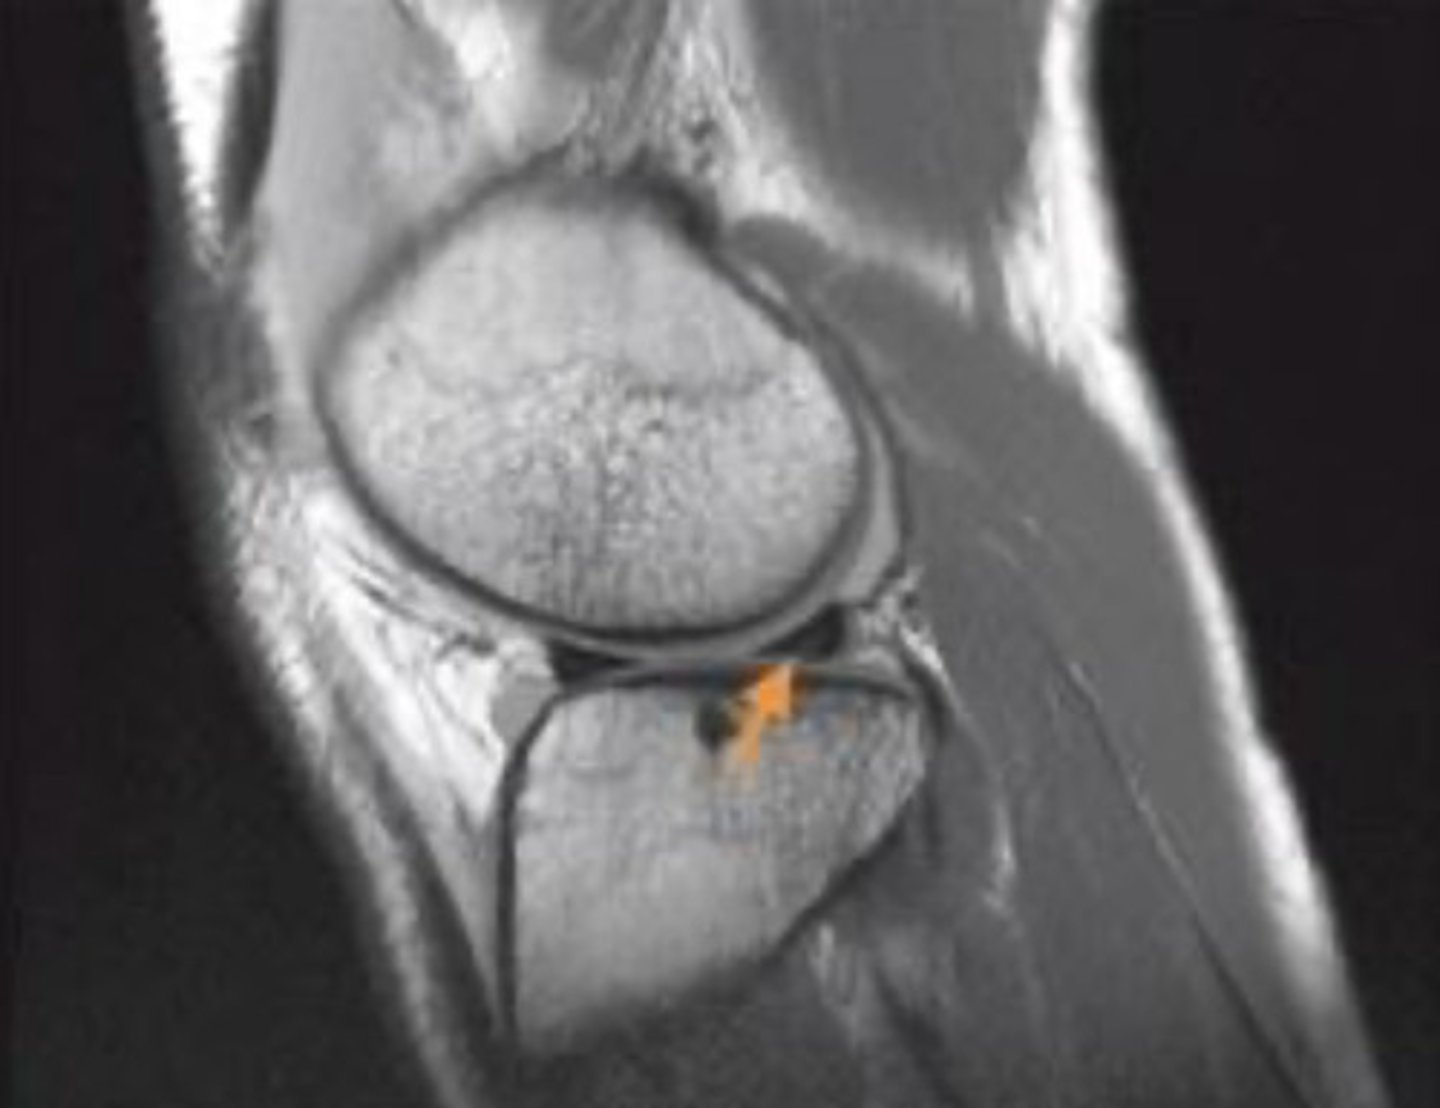

what structure is indicated by the orange arrow?

lateral meniscus, posterior horn

identify the view of this MRI

coronal view